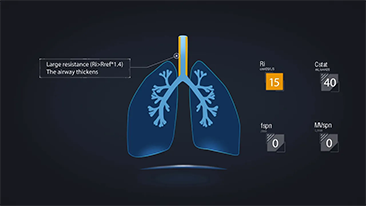

Das Beatmungsger?t im Einzelnen richtig einzustellen, ist bei der Behandlung von Patientinnen und Patienten mit Atemwegserkrankung von entscheidender Bedeutung . Da diese Einstellungen in Bezug auf s?mtliche Parameter von einem Arzt oder einer ?rztin vorgenommen werden, h?ngt ihre Angemessenheit direkt von deren Wissen und der Erfahrung, die sie mit solchen Einstellungen gesammelt haben, ab. In den letzten 20 Jahren hat sich der in der BeatmungsunterstĂŒtzung verfolgte Ansatz grundlegend weiterentwickelt. Ausgehend von den BedĂŒrfnissen der Praxis wurden zahlreiche Beatmungsmodi und Tools zur EntscheidungsunterstĂŒtzung entwickelt, die Zeit einzusparen und Fehler zu vermeiden helfen.

Die 3-in-1-Beatmungsger?te der SV-Serie bieten High-Flow-Sauerstofftherapie, nicht-invasive und invasive Beatmung und vereinen Verl?sslichkeit, Vielseitigkeit und leichte Bedienbarkeit. Die zahlreichen au?ergew?hnlichen Lungenschutzfunktionen und Tools zur EntscheidungsunterstĂŒtzung sollen das Risiko von Kreuzinfektioenn verringern und die Arbeit der Pflegerinnen und Pfleger erleichtern.